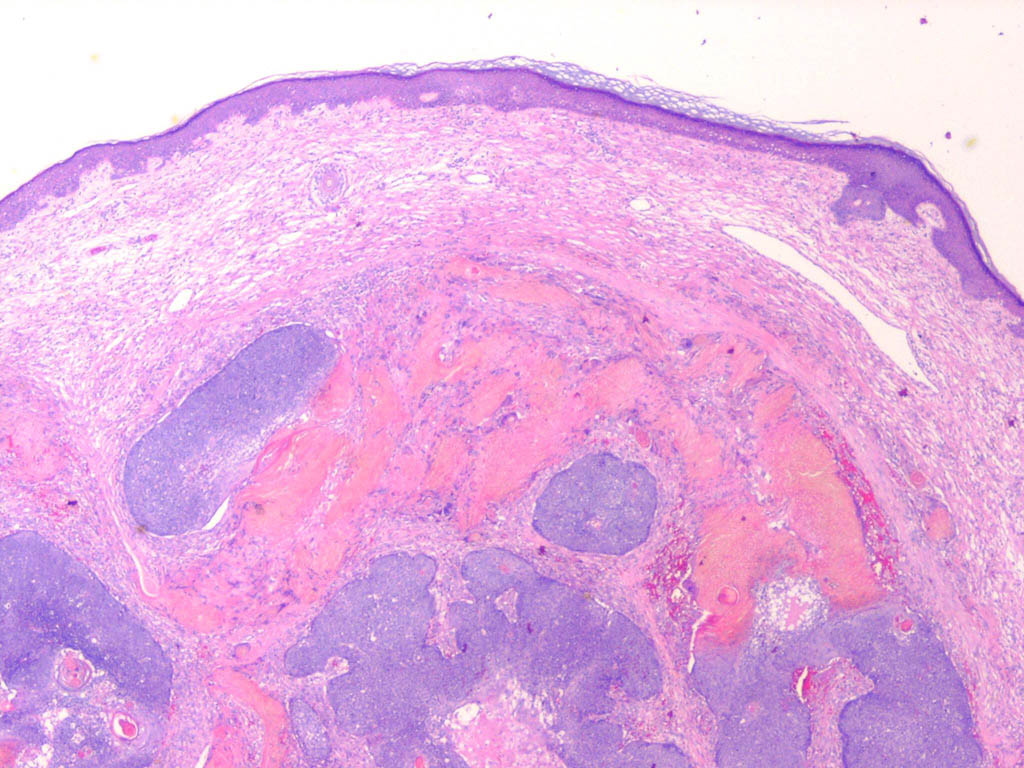

Pilomatricoma shows a spectrum of morphologic features that mainly reflect different evolutionary stages. Early and well-developed pilomatricomas reveal variably sized, round to oval cystic lesions lined by a basaloid epithelium at the periphery and filled in the center with masses of eosinophilic, faulty hair matrix material containing “shadow” (“ghost”) cells

Basaloid (matrical) cells show monomorphous round nuclei with one or more distinctive nucleoli and variable numbers of mitotic figures. Foci of squamoid epithelium are sometimes noted within the epithelial lining. Regressing pilomatricomas display haphazardly arranged foci of basaloid cells and shadow cells as well as an inflammatory infiltrate with multinucleated histiocytic giant cells. Granulation tissue is sometimes noted. Old pilomatricomas reveal no basaloid component but show irregularly shaped, partially confluent masses of shadow cells with foci of calcification or ossification. Melanin deposition, trans-epidermal elimination, and extramedullary hematopoiesis have been described in some pilomatricomas. A peculiar variant with relatively large areas of basaloid cells and small foci of shadow cells (“proliferating pilomatricoma”) is occasionally observed in older adults.